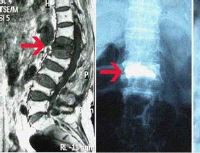

骨显像

一、原理 骨显像剂通过血液循环到达骨表面,应用γ相机和SPECT可使骨骼显像。显像剂沉积在骨骼内的主要机理为:① 通过化学吸附方式与骨骼中的羟基磷灰石晶体表面结合;② …【详细】